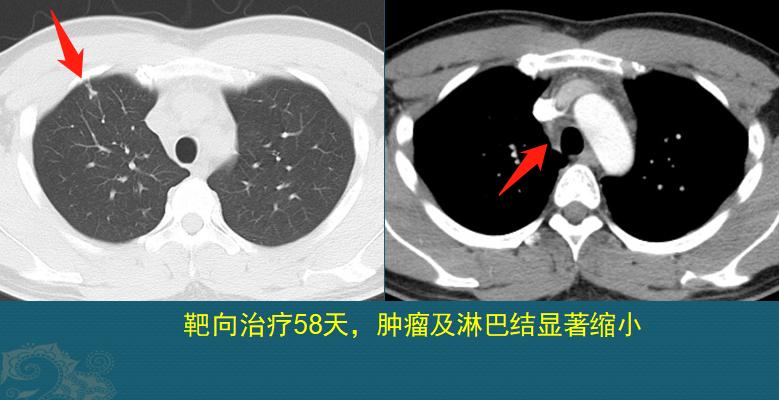

比较幸运的是,他基因检测呈阳性,适合靶向治疗。口服靶向药物第58天复查,肿瘤和淋巴结都明显缩小了:

但愿他能实现长期带瘤生存,太年轻了……